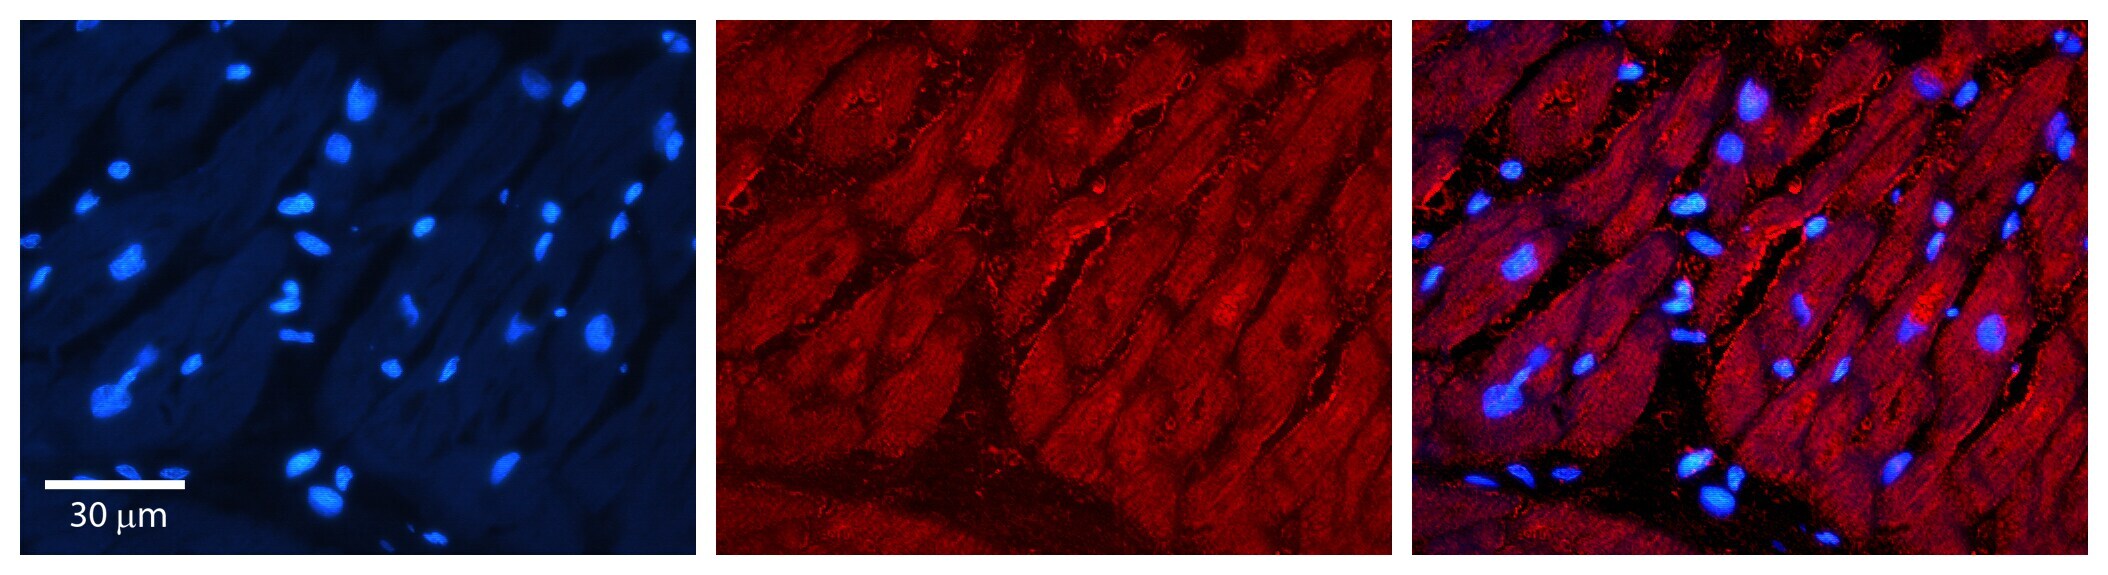

Supportive validation

- Submitted by

- Invitrogen Antibodies (provider)

- Main image

- Experimental details

- Immunocytochemistry was performed on MCF7 cells. Sample was probed with a TIMP3 polyclonal antibody (Product # PA5-70423) with a dilution of 0.2-1.0 µg/mL.